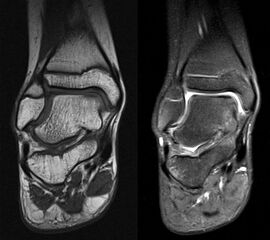

MRT

Die Kernspintomographie hat ihre Stärke in der Darstellung von Weichteilverletzungen. Insbesondere Verletzungen der Wachstumsfuge, des Periosts und der Bänder lassen sich gut visualisieren. Nachteilig ist die Untersuchungsdauer von 20-30 Minuten. Bleibt das Kind während dieser Zeit nicht ruhig liegen, kommt es zu Bewegungsartefakten, welche die Beurteilbarkeit der Bilder beeinträchtigen.

Fugengelenkfrakturen treten typischerweise vor dem 10. Lebensjahr auf, in einer Phase, in welcher die Wachstumsfugen noch weit offen sind. Dieser Frakturtyp betrifft fast ausschließlich den medialen Malleolus. Laterale Frakturen sind extrem selten, teilweise kommt es zu lateralen Bandverletzungen oder Fugenschaftfrakturen der distalen Fibula. Die Frakturlinie verläuft in einer Verlängerungslinie von der medialen Taluskante nach proximal. Häufig stellen sich Verletzungen des Innenknöchels im Röntgenbild schlechter dar, insbesondere wenn die Aufnahmen verdreht sind oder die Ebene der Fraktur bei geringer Dislokation verkippt zur Röntgenebene liegt. Besteht klinisch der geringste Hinweis auf eine Verletzung des Innenknöchels, muss aufgrund der Tragweite der Verletzung durch entsprechende Aufnahmen gegebenenfalls auch Schnittbildverfahren die Verletzung sicher diagnostiziert oder ausgeschlossen werden (Abb. 15).